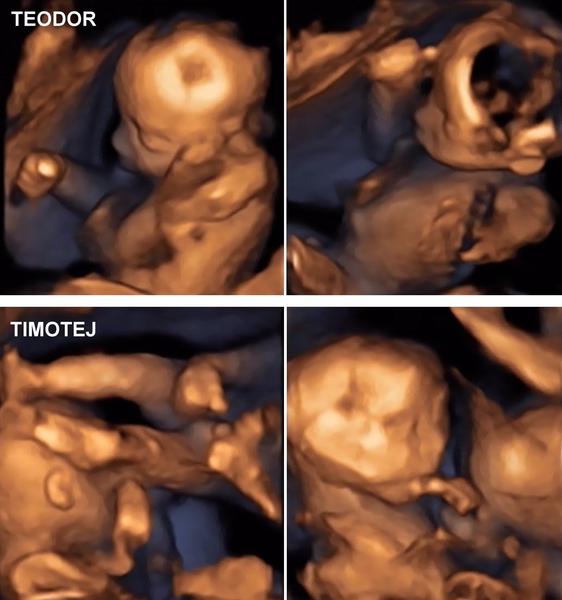

Tak se po dlouhé době hlásím. Velký ultrazvuk za mnou. A čekáme bi-bi chlapečky. 🙂 Oba mají kolem 400g. 🙂

Přidávám vám fotkuu 🙂

@michaelabrazdilova krásní kluci a jak se pěkně ukazují 😀